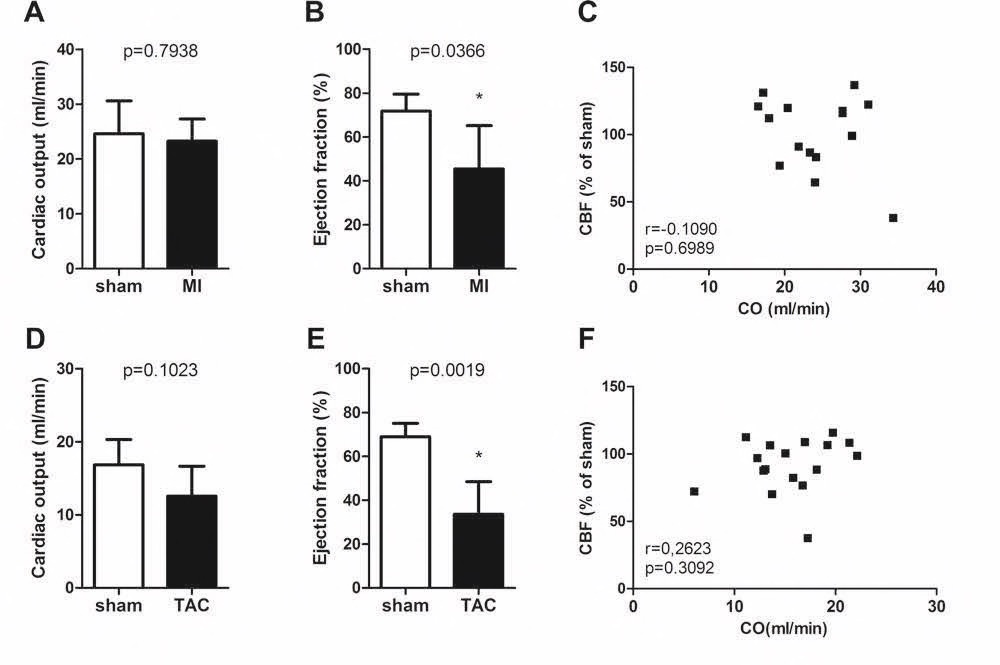

Chapter 6 Figure 2Cardiac function and correlation between cardiac function and cerebral blood flow in MI C57Bl/6 (A-C; n=4, 11) and TAC LDLr-/- mice (D-F; n=5, 12) 12 weeks after surgery. Although the MI and TAC mice did not display a reduced cardiac output (CO) 12 weeks after surgery (A, D), they showed a reduced ejection fraction 12 weeks after surgery (B, E). There was no correlation between the cardiac output and the CBF (C, F). * p<0.05 is significant